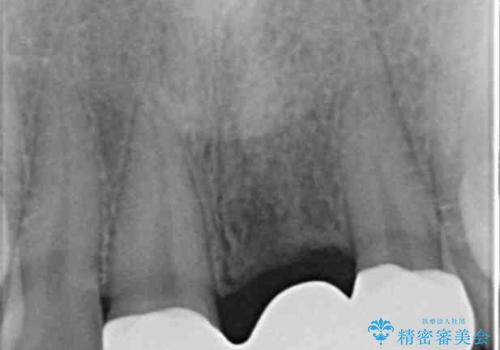

X線写真より、以前に神経の治療が為され変色をきたしている状態であることがわかりました。

根管内の感染は認められないのでセワミッククラウンの製作・装着を行い審美性を改善します。